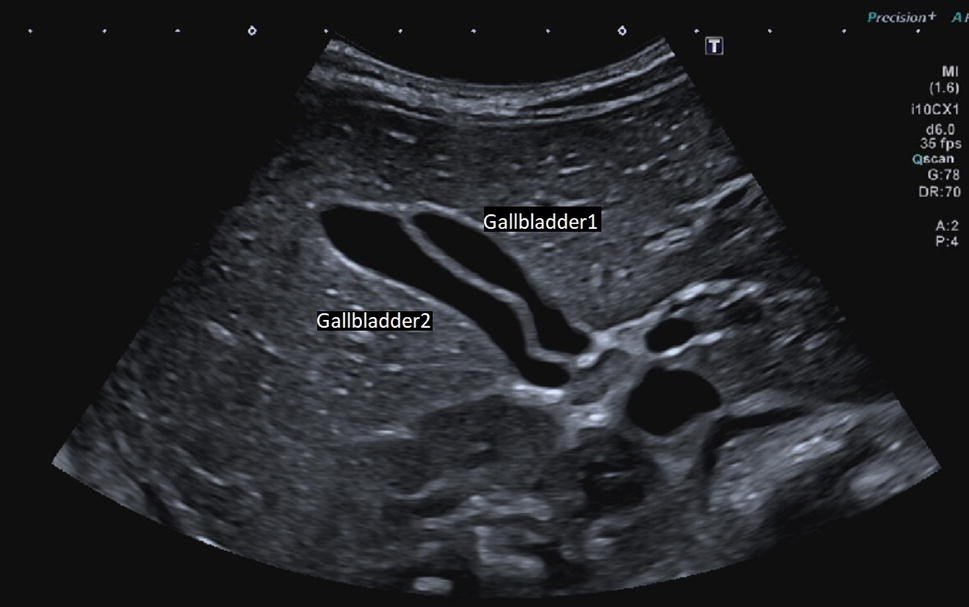

Normal Gallbladder Size on Ultrasound

Normal gallbladder volume on ultrasound indicates:

- Properly shaped

- Clear bile inside

- There are no sludge or stones

- Smooth and thin walls

- Standard size to be used for the fasting state